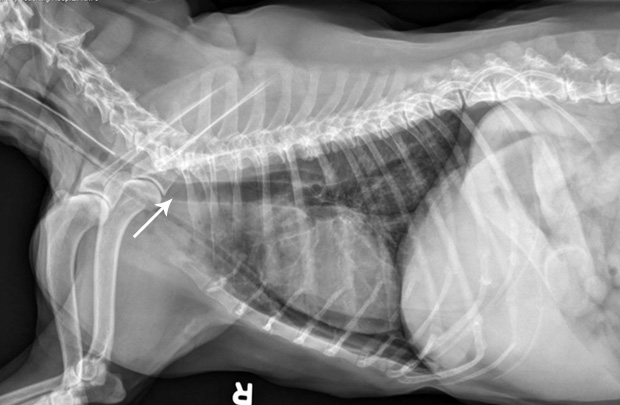

Ensure the tube is properly positioned via lateral radiography (A).

If placement is uncertain, infuse a small amount of nonionic contrast material to differentiate the esophagostomy tube from the endotracheal tube or jugular catheter (B).

FIGURE A